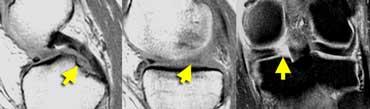

TRÁI: hình dạng bất thường của sừng sau. Một phần bị khuyết. PHẢI: mảnh di lệch trong hố liên lồi cầu.

Rách dọc (2)

Rách hình quai xô (Bucket handle tear)

là rách dọc có di lệch.

TRÁI: sụn chêm có hình dạng bất thường và có mảnh di lệch. PHẢI: Ba cấu trúc trong hố liên lồi cầu: dây chằng chéo sau (1), dây chằng chéo trước (2) và mảnh di lệch (3).

Trên ảnh mặt phẳng coronal, rách hình quai xô dễ nhận biết hơn.

Bình thường, trong hố liên lồi cầu chỉ có hai cấu trúc: dây chằng chéo trước và dây chằng chéo sau.

Bất kỳ cấu trúc nào khác trong hố liên lồi cầu đều là bất thường, và mảnh sụn chêm di lệch là khả năng có thể xảy ra nhất.